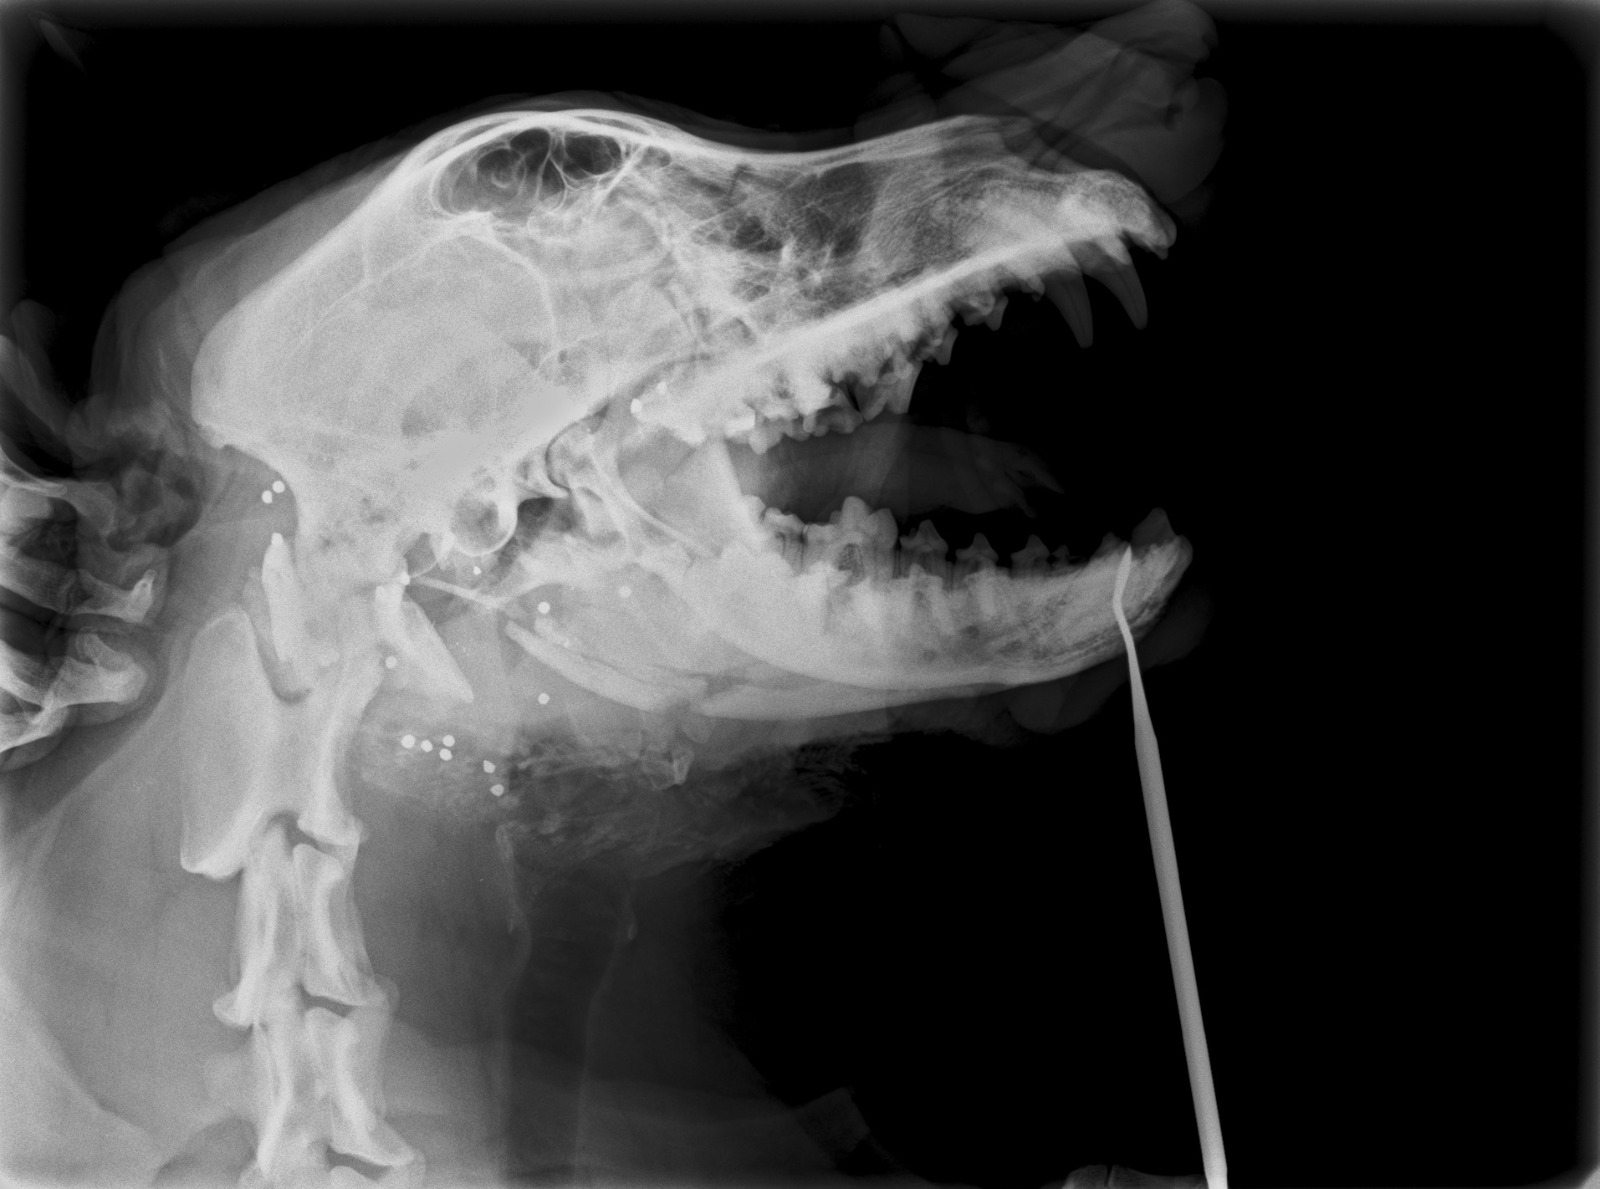

Dada la gravedad, magnitud y evolución de la herida, se sospecha que las lesiones fueron producidas intencionadamente, con maldad y alevosía, y se produjeron en varias ocasiones. No se sabe lo que le hicieron, pero piensan que el primer golpe le destrozó la mandíbula y la boca por completo y debió ser con algún objeto contundente y duro. Al no conseguir “acabar con su vida”, le dispararon varias veces, desde muy corta distancia, en la cabeza (que son las balas que se ven en sus radiografías). Recibió muchos disparos, lo que acabó por destrozarle la mandíbula, el maxilar, los huesos nasales y la boca.

Al día siguiente fue llevada al hospital veterinario donde le realizaron una intervención quirúrgica para valoración del daño, limpieza exhaustiva de la herida y cierre parcial de la misma dejando drenaje. La infección de la herida era tan grave que no pudieron hacer más. Por el momento, LUZ está recibiendo tratamiento antibiótico intensivo, antiinflamatorios y analgésicos para control de la infección y, según evolucione, se planteará realizar otra cirugía para reparación de fractura mandibular.